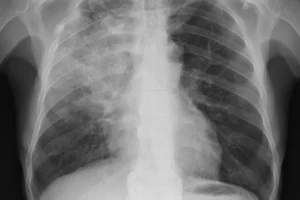

Чем страшна вентилятор-ассоциированная пневмония (ВАП)

Аппарат ИВЛ — незаменимый помощник при тяжелых респираторных заболеваниях, в том числе пневмонии. Интубация трахеи — это одновременно и помощь, и стандартная процедура при нарушениях дыхания. При длительном применении (не менее 48 часов) риск заражения пациента микрофлорой медицинского учреждения с развитием вентилятор-ассоциированной пневмонии (ВАП) достигает 8-28%. Это составляет от 10% до 50% смертей среди пациентов …